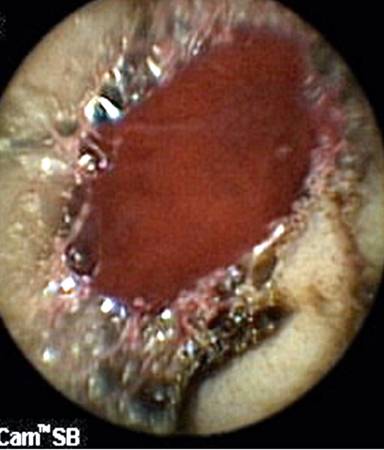

Capsule endoscopy (Given Imaging Ltd., Yoqneam, Israel) was performed after overnight fasting and preparation with polyethylene glycol ingestion and revealed the presence of fresh blood in the proximal jejunum along with a pool of fresh blood with no underlying ulcer (Figure 1). The major papilla was not identified on the capsule endoscopy. A push enteroscopy was subsequently performed which revealed the presence of fresh red blood in the distal duodenum and proximal jejunum. No bleeding lesion was identified. The push enteroscope was immediately withdrawn and a side viewing endoscope (TJF 160, Olympus Optical Co. Ltd., Tokyo, Japan) was inserted. On side view endoscopy, a pool of fresh blood was localized near the papilla (Figure 2). Using a cannula, the area was washed with distilled water and revealed an ooze of fresh blood from a pinpoint defect in the periampullary region. There was no surrounding ulcer or reddish area suggestive of a Dieulafoy’s lesion (Figure 3). Immediate hemostasis was achieved with an endoscopic injection of adrenalin.

Figure 1. Capsule endoscopy: a pool of fresh blood in the proximal jejunum with no underlying ulcer. |